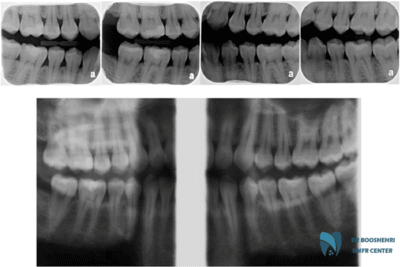

Bitewing radiography is a powerful tool in dentistry that allows dentists to examine gum diseases and hidden problems in the mouth. This technique, aided by precise two-dimensional images of the teeth and surrounding tissues, including the gums, enables specialists to identify diseases that are not detectable with the naked eye. Gum diseases, which are often asymptomatic in their early stages, can progress silently and lead to more serious issues.

Bitewing radiography is one of the best tools for the early detection of gum diseases due to its high capability for imaging between teeth and the supporting bones. This method helps dentists recognize early signs of diseases such as bone resorption and gum inflammation. The sooner these issues are identified, the quicker and more effective their treatment will be.

Studies have shown that bitewing radiography, due to its high accuracy and ability to display precise details—especially in the posterior areas of the teeth—is a key tool for diagnosing periodontal diseases and bone resorption. This method, due to its simplicity and lower radiation dose compared to other methods such as panoramic radiography, not only provides high accuracy but also reduces imaging time and costs. For this reason, bitewing radiography is commonly used in epidemiological studies to extensively assess gum diseases.

Silent gum diseases refer to conditions that progress without clear and visible symptoms and may only show signs when they require advanced treatment. Bitewing radiography helps dentists identify these silent diseases in their early stages. By closely examining bitewing images, small changes in the gums and supporting bone structures can be detected, which are often not visible to the naked eye.

This method is particularly effective for diagnosing conditions like periodontitis, which can lead to bone resorption and tooth loss. With the aid of bitewing radiography, dentists can quickly take necessary therapeutic actions to prevent disease progression. This early diagnosis can help preserve teeth and maintain gum health, reducing the need for more complex and costly treatments.